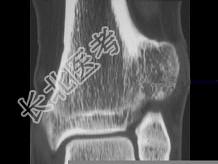

- 单项选择题青少年患者,踝部疼痛, 如图所示,最可能诊断为 ( )

A、软骨肉瘤

B、骨软骨瘤

C、转移瘤

D、骨肉瘤

E、以上都不是